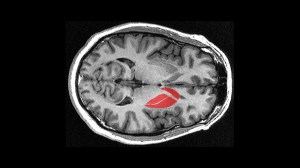

EPFL scientists have identified specific neurons in the striatum that contribute to driving motivated behaviors like movement. The work may help in designing new ways of treating disorders like Parkinson’s disease in the long term. Read more